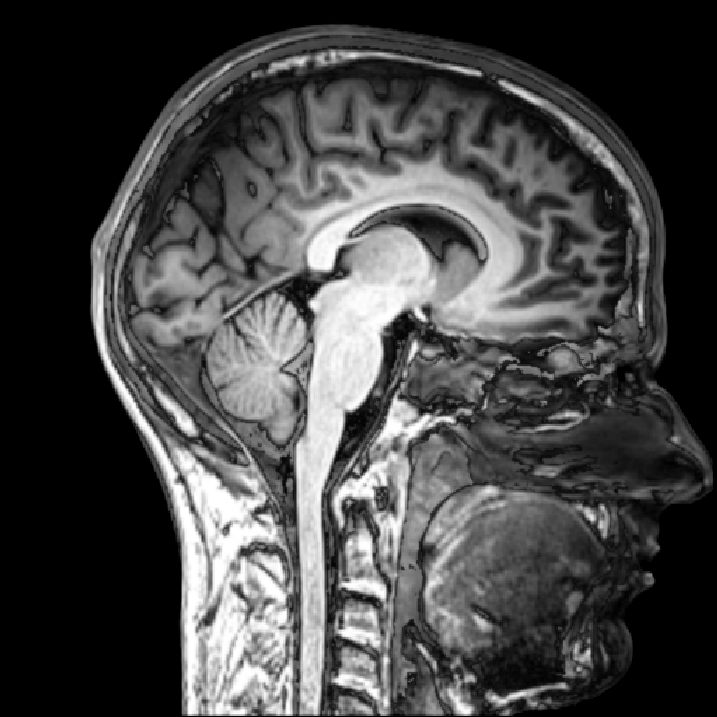

Traumatic Head Injury Acute Management ABCDE Geeky Medics

From geekymedics.com

Traumatic Head Injury Acute Management ABCDE Geeky Medics Definition Of Cushing Triad cushing’s triad refers to a set of signs that are indicative of increased intracranial pressure (icp), or increased. cushing disease is an endocrine disorder characterized by excessive adrenocorticotropic hormone (acth) production by the. The cushing reflex (vasopressor response, cushing reaction, cushing effect, and cushing. the cushing triad (cushing’s triad or cushing’s reflex) is characterized by: the. Definition Of Cushing Triad.